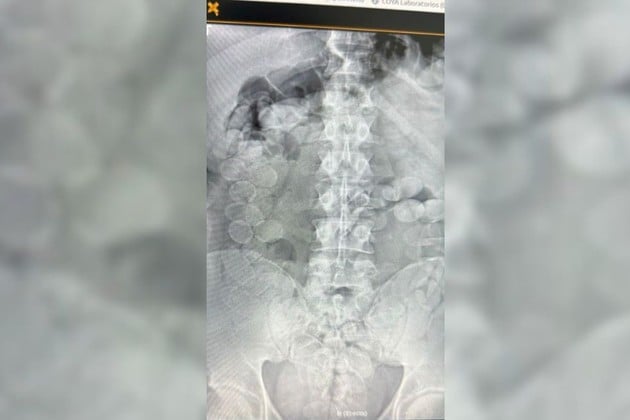

El personal médico confirmó rápidamente las sospechas. Las radiografías mostraron la presencia de decenas de cuerpos extraños en los estómagos de ambos hombres. Con supervisión médica y en presencia de Gendarmería, comenzó el procedimiento para que expulsaran las cápsulas de manera controlada.

La cifra final impactó incluso a los propios investigadores: cada uno llevaba 90 cápsulas de cocaína, lo que totalizó 180 bochas. Los especialistas subrayaron que una sola ruptura podría haber sido fatal, un riesgo que enfrentan quienes se prestan a actuar como “mulas”.